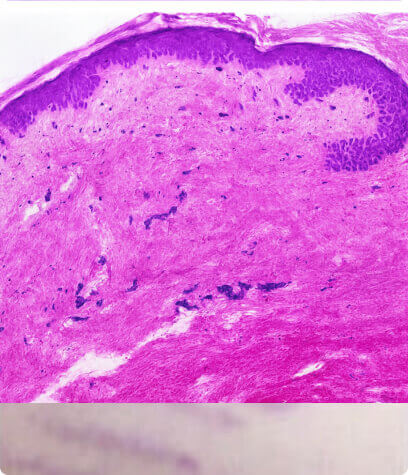

This aging process is accompanied by structural and functional changes in extracellular matrix components such as collagen and elastin. The result in the appearance of fine lines and wrinkles.

Zhang, S., & Duan, E. (2018). Fighting against Skin Aging: The Way from Bench to Bedside. Cell transplantation, 27(5), 729–738.

How it works

- Promotes removal of old damaged collagen

- Induces keratinocytes proliferation that releases growth factors to promote collagen deposition by the fibroblasts and elastin deposition

- Modulates the expression of several genes in the skin (vascular endothelial growth factor, fibroblast growth factor, epidermal growth factor, collagen type I and III) that promote extracellular matrix remodeling